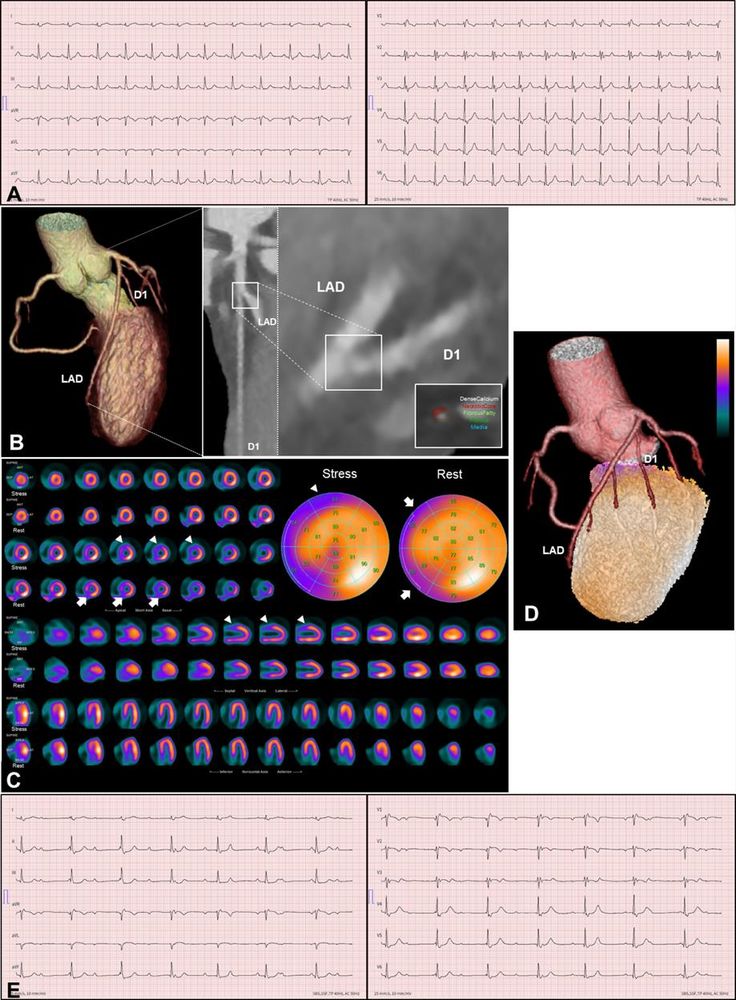

🫀 Pioneering: Discordant perfusion defects & #CAD in cardiac sarcoidosis—multimodality journey at #IJCVI!

🌐

Discordant myocardial perfusion defects and coronary artery disease – a multimodality imaging journey in the natural history of cardiac sarcoidosis

The International Journal of Cardiovascular Imaging - Cardiac sarcoidosis is a rare form of systemic sarcoidosis characterized by formation of non-caseating granulomas in the myocardium, leading to...

doi.org